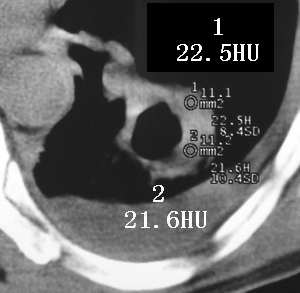

以下是引用sdqzwyx在2005-11-7 19:59:00的发言:[br]双肺弥漫大小不等的粟粒状结节影;肺纹理走行失去自然,粗细不均,边缘不规则,小叶间隔增厚;左上肺示不规则形致密影,从斑块边缘向周围伸出长短不一的致密索条影,临近的血管、支气管和叶间胸膜等结构受牵拉移位;左下肺示不规则团块状影,其内示空洞,洞内壁尚光整,左侧胸腔积液。右肺下叶背段亦示部分病灶融合。双肺可见局限性肺气肿。[br]诊断:结合病史符合三期矽肺表现(少数矽肺纤维斑块内可以形成空洞,一般认为是斑块中央感染引起坏死所致)但尘肺病人易合并肺结核,诊断可为三期+tb。所以此病人应进一步检查是否合并结核。